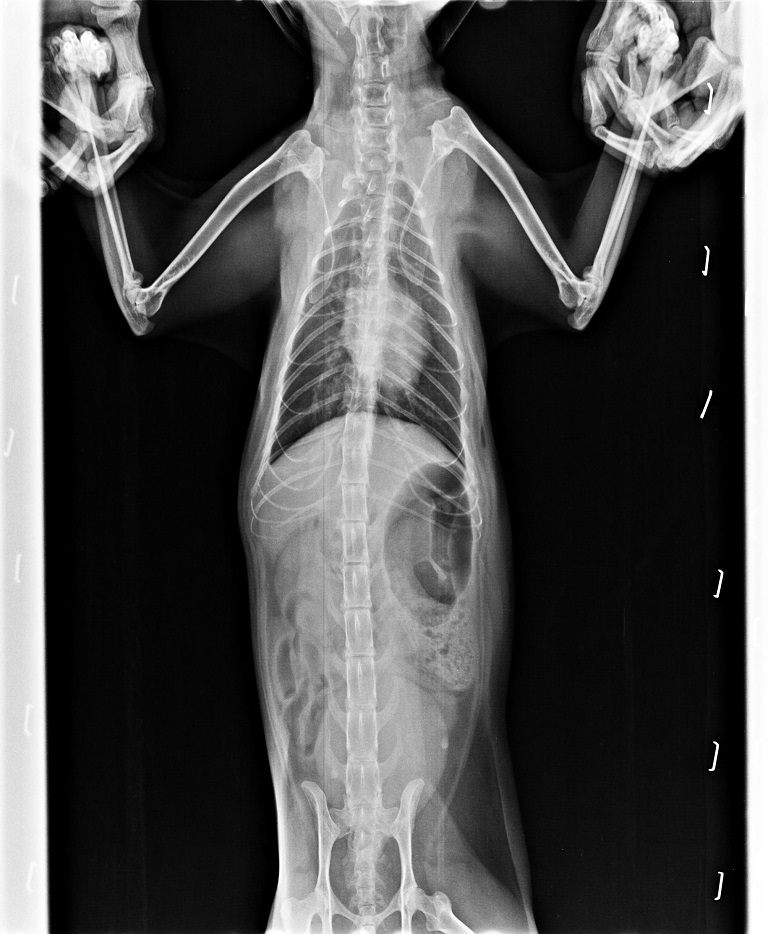

很難想像,小小的身軀承受了多次血液生化檢查、、耳垢檢查、糞檢、X光片、血巴東核酸診斷檢驗、皮下點滴注射、口服抗生素、化痰藥、抗組織胺、食慾促進劑、腸內寄生蟲驅蟲、肝腦錠、消化酵素、消炎眼藥水、耳藥水、噴霧,這些對她來說都是精神上的壓迫,肉體上的折磨,而她總是那個靜靜的、帶點惶恐的樣子躲在角落,承受著一切。